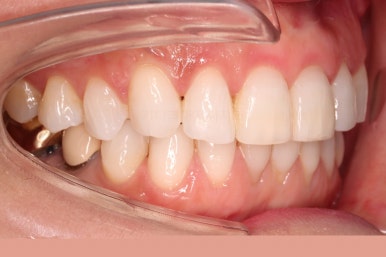

윗니에만 장치를 부착하고 부분교정을 시작했습니다.

환자분이 연산동부분교정 선택하신 장치는 엠파워 클리어라고 하는 자가결찰 세라믹 장치입니다.

장치 부착한 모습 참고해 주시고요.

적절하게 치간삭제를 일부 동반하여 빠른 시일 내에 가지런하게 해드리고 마무리를 했습니다.